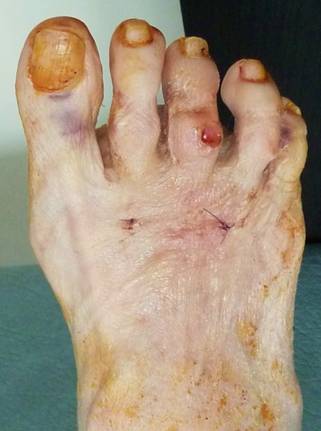

Судя по фотографиям, укорочение 2 пальца не является косметически значимым. Есть его молоткообразная деформация наряду с варусным отклонением 3 пальца, который уже "подлез" под второй, и вальгусной деформацией дистальной части 1 пальца (hallux valgus interphalangeus). То есть, расстояние между 1 и 3 пальцами уменьшено. Значит вмешательство должно быть направлено не только на устранение молоткообразной деформации 2 пальца, но и на формирование пространства для него между 1 и 3. Оптимальным мог бы быть следующий набор хирургических действий: чрескожная удлиняющая тенотомия разгибателей и поверхностного сгибателя 2 пальца; коррегирующие чрескожные остеотомии оснований основных фаланг 2 и 3 пальцев и дистальной трети основной фаланги 1 пальца. Если не оперируете чрескожно, операции на 2 и 3 пальцах можно сделать через маленькие разрезы узкой пилкой или узким долотом, а на 1 пальце любым доступным Вам способом. Фиксировать или нет остеотомии зависит от Ваших предпочтений. При правильно наложенной и удерживаемой в течение 3-4 недель повязке внутренняя фиксация таких остеотомий не обязательна. Операция на трех пальцах выгодна еще и тем, что позволит пропорционально укоротить их, сохранив имеющееся взаимоотношение длин.

Палец приподнят над остальными за счет избыточного тыльного сгибания в плюснефаланговом суставе. Если уж думать о резекции, то о резекции основания основной фаланги, а не головки. Иначе основная фаланга так и останется приподнятой, а палец как мешал, так и будет мешать. Только станет короче и тугоподвижнее за счет фиксации спицей. После подобной операции палец вполне можно эффективно удерживать в нужном положении повязкой. А при необходимости положение пальца во время перевязки можно легко подкорректировать. Во вложенном файле пример возможности удержания пальцев повязкой в гораздо более серьезной ситуации.

Здесь стопа до и через неделю после вмешательства на первой перевязке. На операции были выполнены субкапитальные остеотомии 2-4 плюсневых костей, оснований основных фаланг 2-5 пальцев и средних фаланг 2-3 пальцев. И даже при таком объеме нужды в фиксации спицами нет.

Что видим: укорочение 2 плюсневой кости, лёгкую молоткообразную деформацию 2 пальца, незначительное варусное отклонение 3 пальца. И всё! Длина 1 пальца, длины всех остальных плюсневых костей симметричны (померяйте с линейкой физическую длину – она отличается в пределах 2 мм, т. е. в пределах погрешности измерения и рентгенологической позиции). Hallux valgus’а нет никакого, даже interphalangeus (посмотрите на другую стопу). Диагноз: брахиметатарзия 2 плюсневой кости. Соответственно, нужно эту самую кость удлинять. А не укорачивать (разворачивать, отклонять) соседние кости!!! Этими вмешательствами даже теоретически невозможно решить проблемы пациентки, а ведь у каждой операции есть последствия и риски.

Пациентку, скорее всего, беспокоит косметический дефект. И молоткообразная деформация 2 пальца - уже есть гиперкератоз на тыле проксимального межфалангового сустава. Варусное отклонение 3 пальца возникло компенсаторно, оно минимально и, скорее всего, пациентку не беспокоит.